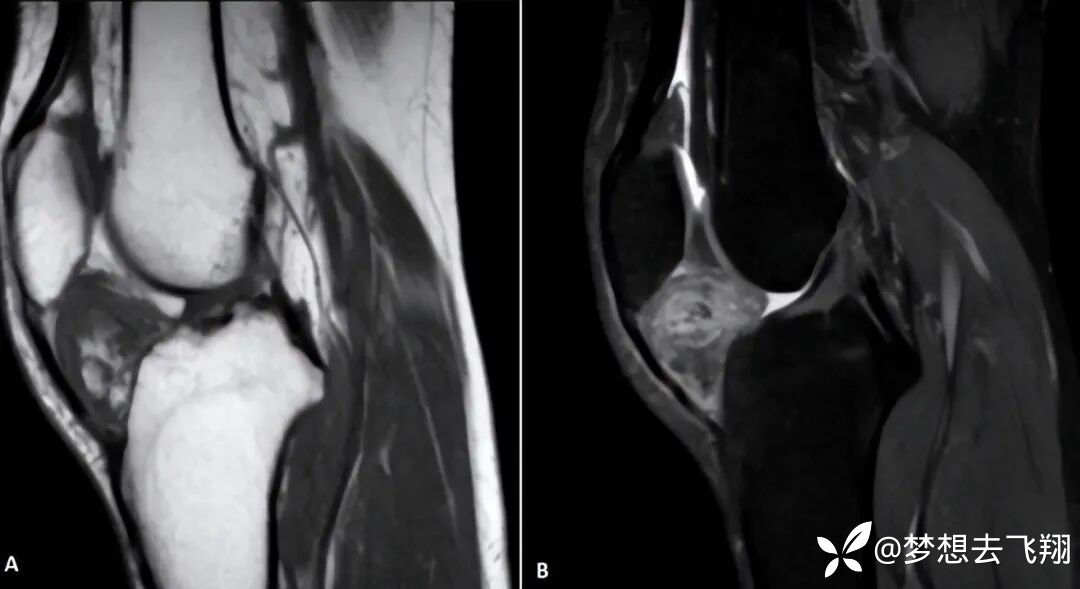

图9:40岁单侧进行性右侧性膝痛,临床检查时伴有关节积水症上下楼梯时加重。标准X线片正常。参考7

图9的解释:MRI显示Hoffa脂肪肥大为异质性低信号T1(A),高信号T2为脂肪饱和度(B),钆注射后异质性增强。